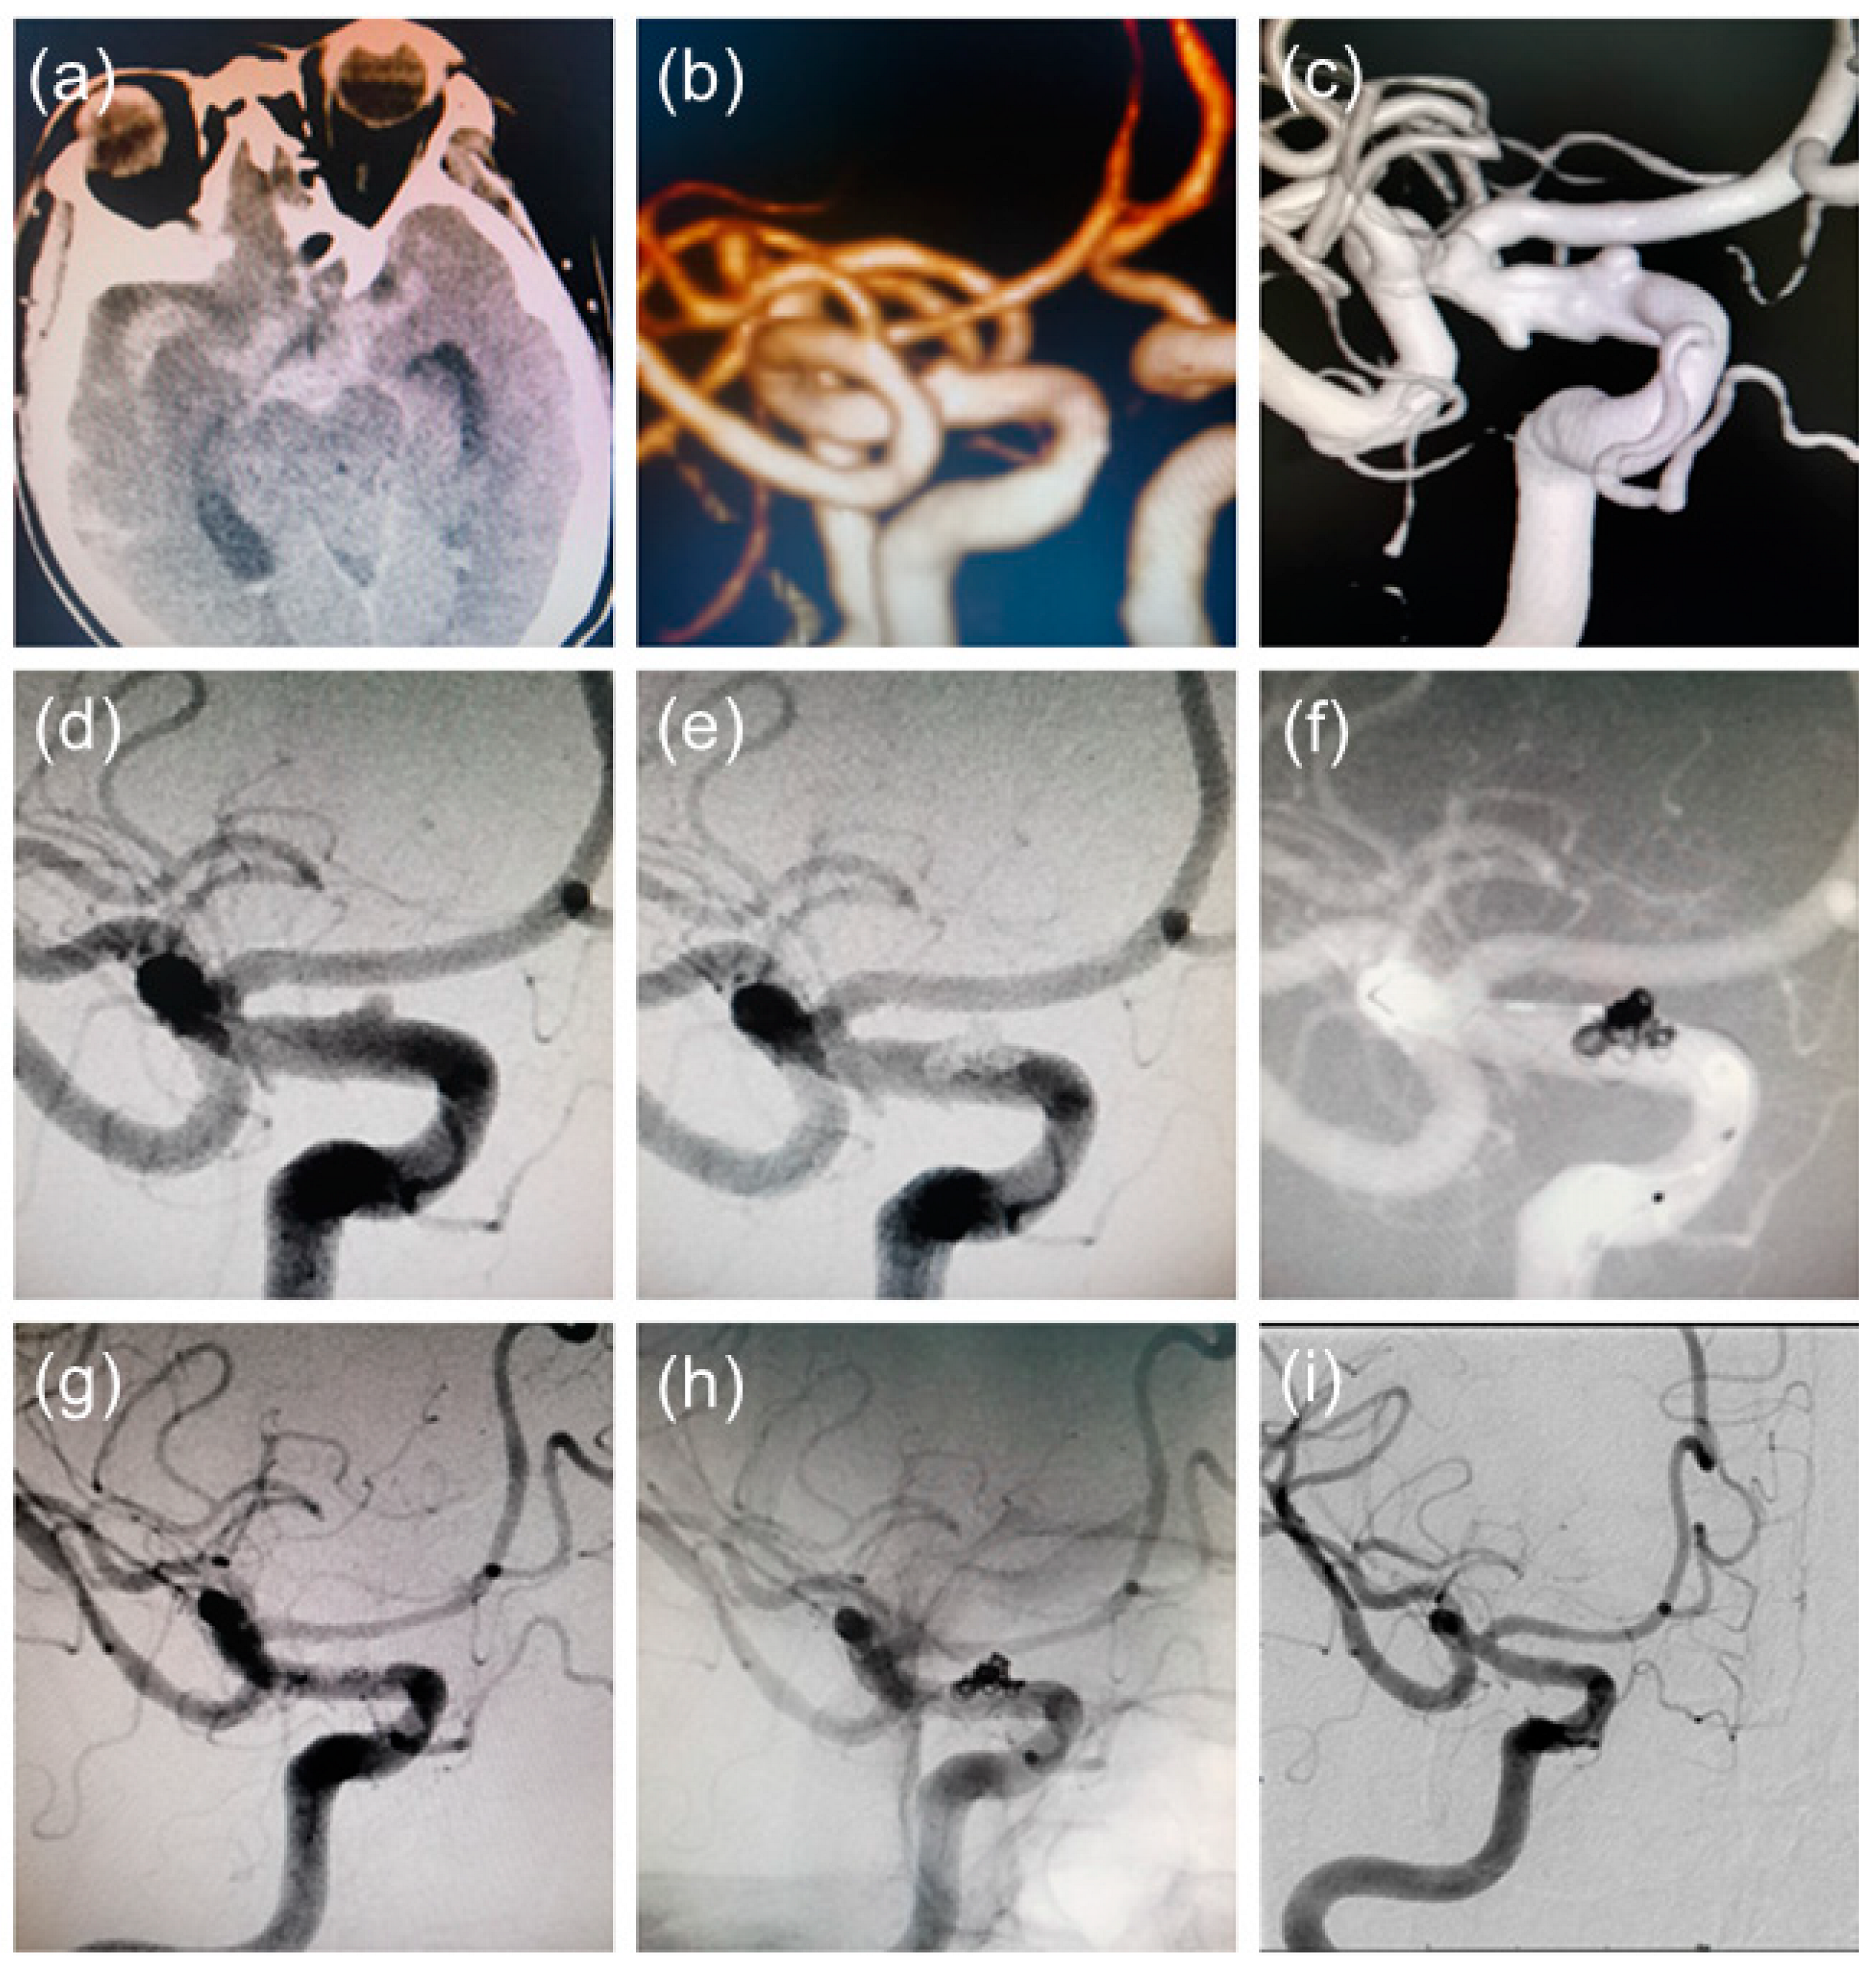

4. Typical Case